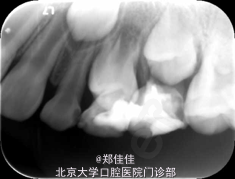

检查:64DO牙色充填体,边缘密和,叩痛(+),IO松动,颊侧牙龈红肿,有扪痛 16O龋洞,可及腐质,质软,探诊不敏感,叩痛(-),不松动,牙龈未见异常

诊断:64慢性根尖周炎 16O中龋 治疗计划:1.64拔除 2. 16OPRR 处置:1.签知情同意书 2. 16O上橡皮障,去腐净达牙本质中层,全酸蚀,SL-Bond,超钻+流动树脂+窝沟封闭剂充填,调合,修形,磨光 3.54必兰局麻下分龈,钳拔,离体牙完整,下方探及24牙冠,复位,压迫,止血 4.医嘱,2周后复查